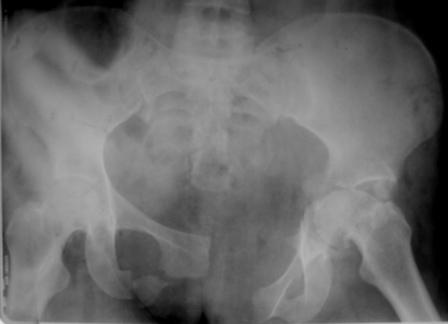

Уважаемые коллеги! Пациентка 32 года с застарелым повреждением таза, после остеосинеза лонного сочленения пластиной. Посоветуйте с выбором тактики и методик лечения.

Получила травму в феврале 2004г в г.Лобытнанги ЯНАО Тюм.обл. Через неделю после поступления выполнен остеосинтез лонного сочленения пластиной. 1,5 месяца на скелетном вытяжении. В последующем ходит при помощи костылей с нагрузкой на правую ногу. Имеется нестабильность половин таза, неправильно-консолидированный перелом левой вертлужной впадины, невропатия седалищного нерва слева. В результате невропатии седалищного нерва сформировалась эквинусная установка левой стопы, парестезии по подошвенной поверхности.

Клинически: ходит на костылях с нагрузкой на правую ногу. Левая стопа в эквинусе. Осевая нагрузка на левую н\конечность болезненна в области левого тазобедренного сустава, при прикосновениях к подошвенной поверхности стопы у пациентки чувство зжения. В левом коленном суставе полный обьем движений, в левом тазобедренном резко ограничено отведение и ротация, укорочение левой н\конечности на 2,5 см. При полипроекционной и функциональной Р-графии выявлена нестабильность левого КПС и лонного сочленения, консолидированный в порочном положении поперечный оскольчатый перелом левой вертлужной впадины с центральным смещением головки бедра. Нами выполнена коррекция деформации левой стопы. Планируется выполнить введение 2 канюлированных илиосакральных винтов слева, реостеосинтез лонного сочленения реконструктивной пластиной, после заживления ран - тотальное эндопротезирование левого тазобедренного сустава.